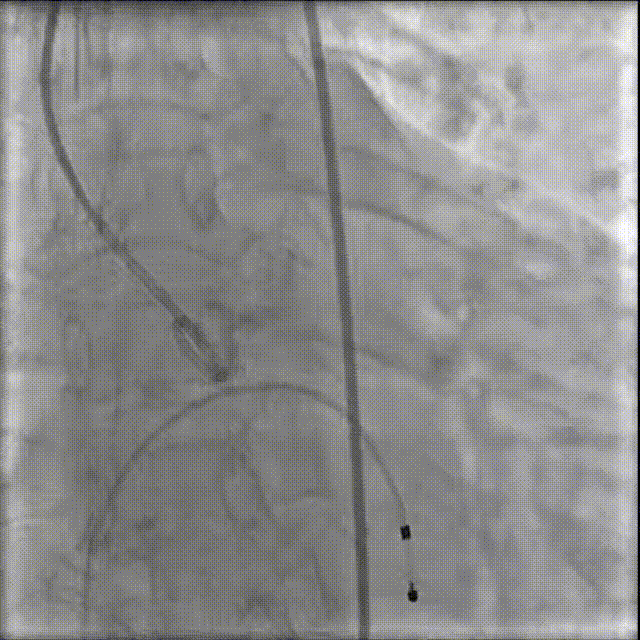

修建成教授 南方医科大学南方医院(点击查看专家详细简历) 细微之处防未然,创新携手寸寸安: 愈知临床无小事,任何风险的蛛丝马迹,都可能牵动全局。我常对团队说,真正的严谨,是将所有潜在 scenario 视作必然,在术前便一一拆解、化解 —— 如同在堤坝溃决前便筑牢每一寸基石,让风险连萌芽的机会都没有。 此次应用全球首创的预装干瓣,是基于对患者的综合考量,拥抱创新,实践创新,让创新携手助力“万全之策”的重要环节。 术前推演需要结合器械的特性:深度了解才能得心应手,结合患者基础病的相互影响并落实到术后 72 小时的并发症预警,每个环节都要像精密齿轮般咬合无误。这份 “穷尽万一” 的准备,从来不是对完美的苛求,看似耗时费力,实则是对生命最质朴的承诺 ——以医者的周全,携手创新的产品,为患者的万无一失不断努力! 患者病史 因 "反复胸闷伴活动后呼吸困难 3 年" 入院:患者 3 年前无明显诱因反复出现胸闷,部位在前胸,有憋气感,间有心悸,伴有活动后呼吸困难;外院就诊,查心脏彩超示 "主动脉狭窄、二尖瓣关闭不全"; 既往有高血压 20 余年,长期服用氨氯地平阿托伐他汀钙片降压治疗;有糖尿病 1 年,长期服用二甲双胍、阿卡波糖降糖治疗。 术前超声提示:主动脉瓣增厚、钙化并狭窄(重度)及关闭不全(轻度) 术前超声提示:主动脉瓣增厚、钙化并狭窄(重度)及关闭不全(轻度) 术前CT Type1型(R-N)二叶瓣,中度钙化集中在左窦瓣叶边缘及右无交界处,主动脉根部直径21.6mm,LVOT直径22.2mm,瓣上限制逐渐增大;双侧冠脉开口高度可,瓣叶短,窦部宽度足够,双冠VTC空间>4mm,预估冠脉风险小。 左室腔小,室间隔膜部短,有一定PPI风险;外周双侧入路无明显迂曲,双侧髂外动脉存在散在钙化、股动脉直径大,右股低分叉,能够支持20F大鞘通过。 手术策略 推荐右侧股动脉为主入路,放置20F大鞘,左侧为辅助入路,常规穿刺;使用20球囊预扩,预装AV23瓣膜;左右重叠位:RAO 1° CAU 28° ;右窦居中位:LAO 22° CAU 0° ;左冠切线回调:LAO 35° CRA 17° ;心室小,术前术中积极补液调整容量,做好循环崩溃处理准备。 手术过程 主动脉根部造影 20mm球囊预扩 - 无腰无漏 瓣膜初始定位 工作位观察瓣膜 - 冠脉通畅,位置合适 最终造影观察 - 无瓣周漏、挂钩处于最右方-Commisural Alignment 术前压差120mmHg,术后压差2mmHg。 Prostyle A®预装干瓣——助力临床最优化解决方案: 平衡的径向支撑力:该病例为TYPE 1型二叶瓣,对产品的径向支撑力是一种考验,术后影像彰显Prostyle A®综合设计带来平衡的径向支撑力,轻松应对高钙化病变,符合中国国情,为二叶瓣患者带来信心保障; 轻松过弓,精准可控:该病例主动脉弓角度可,但弓距小,考验产品的通过性能,术中顺利过弓,未使用snare轻松过弓; 预装干瓣 便捷顺安:金仕生物专利抗钙化技术运用纳米技术去除组织内的细胞碎片和磷脂,封闭游离醛基,从根本上阻断了瓣膜钙化的多项因素,显著提升了瓣膜的耐久性;同时,相比较传统戊二醛保存方式,干式存储最大限度的保留心包的亲水亲油平衡,还原组织天然曲柔性,进一步保障了瓣叶开合,保证长期耐久性。